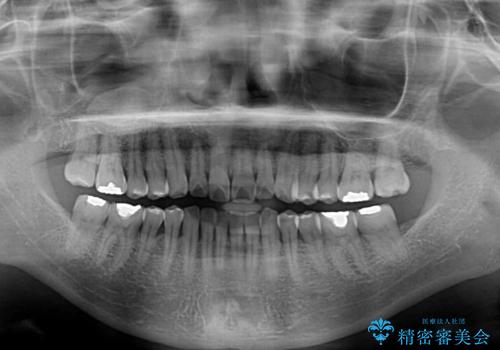

- 上下前歯のデコボコを気にして来院された患者様です。

安価なインビザラインパッケージを用いての治療を希望されており、デコボコの程度が中等度であったため、インビザライン・モデレートを用いて矯正治療を行うこととしました。